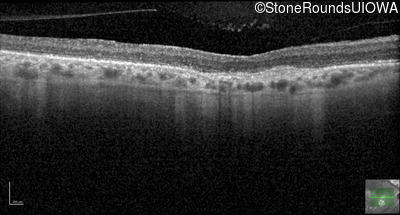

Optical Coherence Tomography - Right - 20/100

Exemplar / OCT Stack

OCT Stack

Optical Coherence Tomography - Left - 20/100

Infrared Fundus Photograph - Right - 20/100

Exemplar

Infrared Fundus Photograph - Left - 20/100